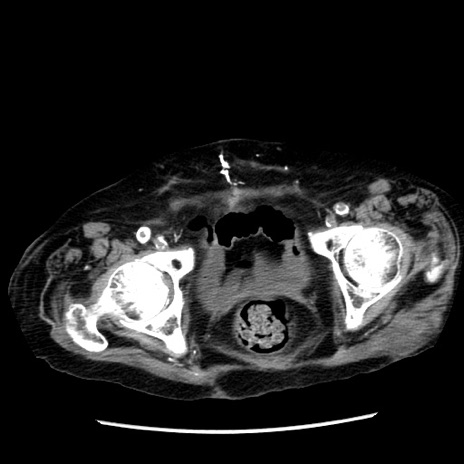

症例14(横断像)

【症例】 90歳代女性

【主訴】 腹痛・嘔吐

【現病歴】今朝から左側腹部痛を認めた。 経過観察していたが、嘔吐を認めたため来院。

【既往歴】 子宮癌術後

【身体所見】 意識清明、BP 127/54mmHg、P 98bpm Sp02 95%(RA)、BT 35.8°C、腹部平坦・軟腸ぜん動音聴取良好、右下腹部圧痛(+) 反跳痛なし

【データ】WBC 9800、CRP 0.46